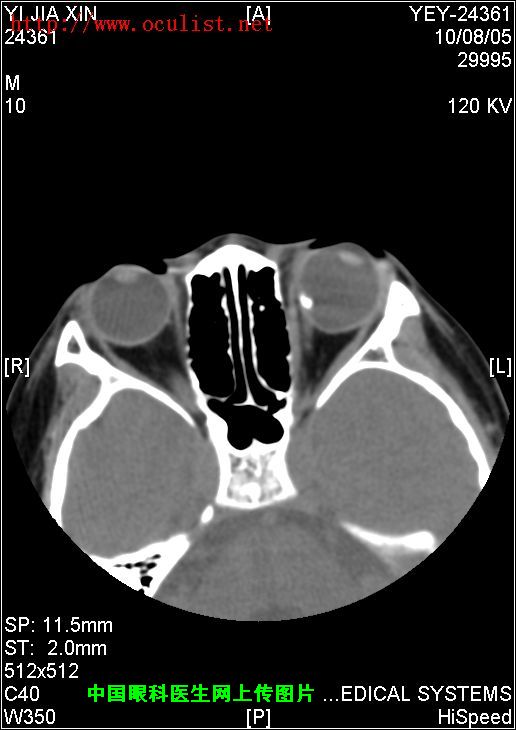

[组图]患者男,9岁,发现左眼外斜9年         ★★★

患者男,9岁,发现左眼外斜9年

患者男,9岁,发现左眼外斜9年,检查:左眼视力0.01(矫正不应),左眼外斜400,角膜、晶状体未见异常,眼底如下图,CT如下图,RMI暂无,请分析一下该患儿的诊断?

眼底图和CT片: